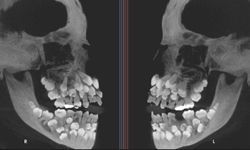

一般成人擁有的牙齒數量為28~32顆,而擁有超過這個數量的症狀就叫做多齒症Hyperdontia,有可能為基因遺傳影響,也有可能是後天環境使然,是種常見的症狀,多齒症牙齒不一定會外露,多數是深藏在骨骼內,而多出的牙齒數量可能會擠壓牙床生長空間而造成暴牙,或影響已生長的牙齒造成牙縫。

而一般的多齒症都可以用手術解決,牙醫只要透過X光線掃描也可以及早發現是否擁有該症狀,但是多齒症當中最稀少的摩爾型多齒症Molar-type,照片可是會讓人看了感覺非常不舒服!